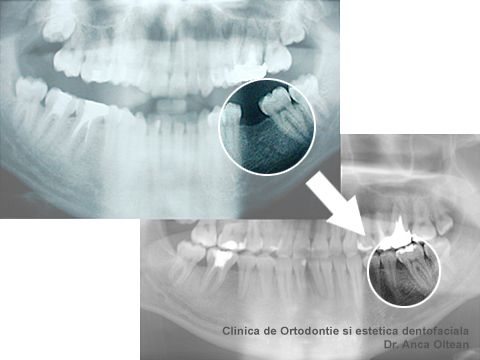

De cele mai multe ori insa, la pacientii adulti problemele dentare se complica prin migrari ale dintilor consecutive unor extractii dentare vechi, netratate sau existenta unei parodontopatii. In aceste situatii, tratamentul ortodontic este doar o etapa in cadrul tratamentului complex de reabilitare orala. Cu aparatele dentare se pot corecta axele inclinate ale unor molari in vederea inserarii unor implanturi sau chiar inchiderea biologica a unor spatii post-extractionale vechi, prin deplasarea molarilor.

Migrare dinti, inainte de tratamentul ortodintic (sus) si dupa tratamentul ortodontic (jos)